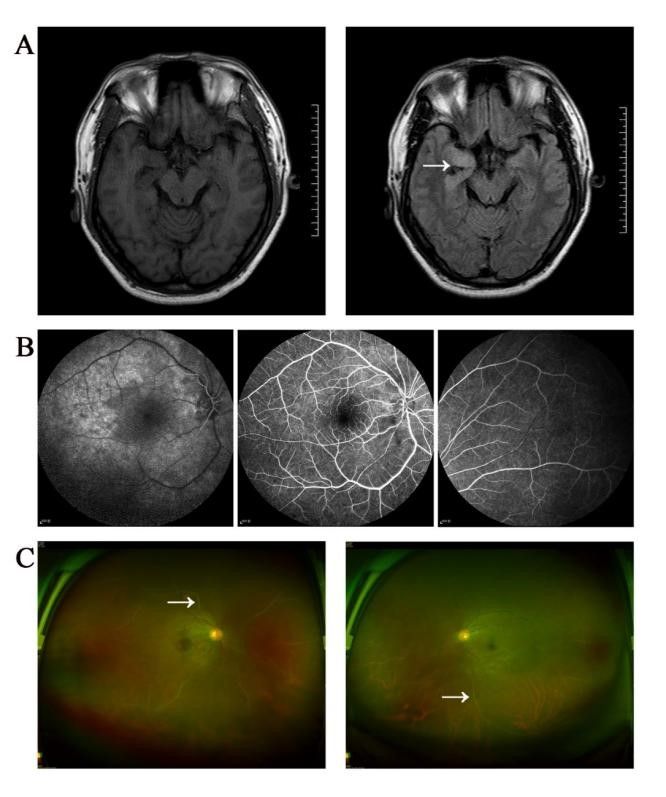

图示:(A):磁共振成像T2-FLAIR显示颞叶前部和内侧部有略高信号(箭头所示);(B):眼底动脉造影显示动脉充盈迟缓,部分血管闭塞,血流呈串珠样改变;(C):眼底镜检查显示玻璃体混浊,视网膜周边部分血管闭塞,呈“白线样”特征(箭头所示)。